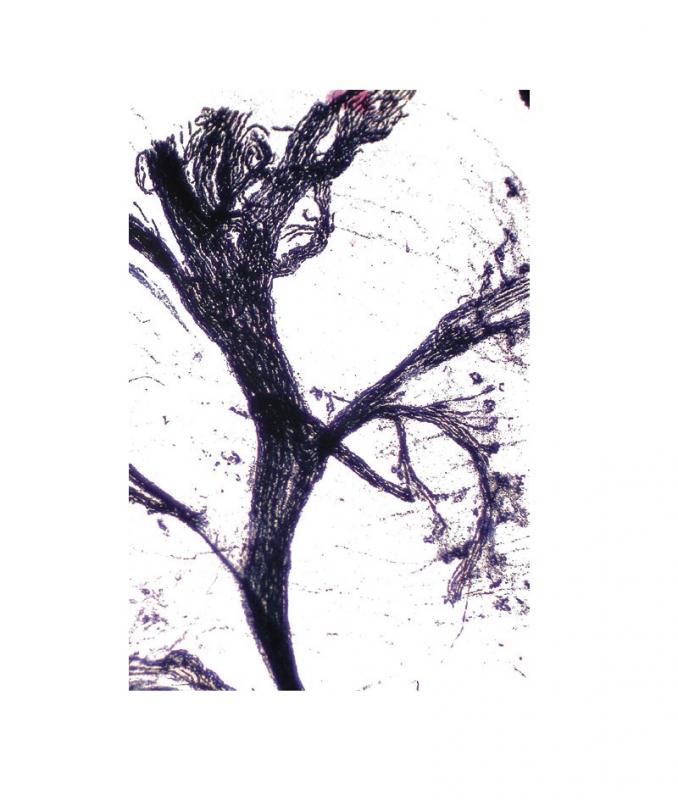

Préparation microscopique: Nerf osmie lapin CL

Référence Interne : S60425